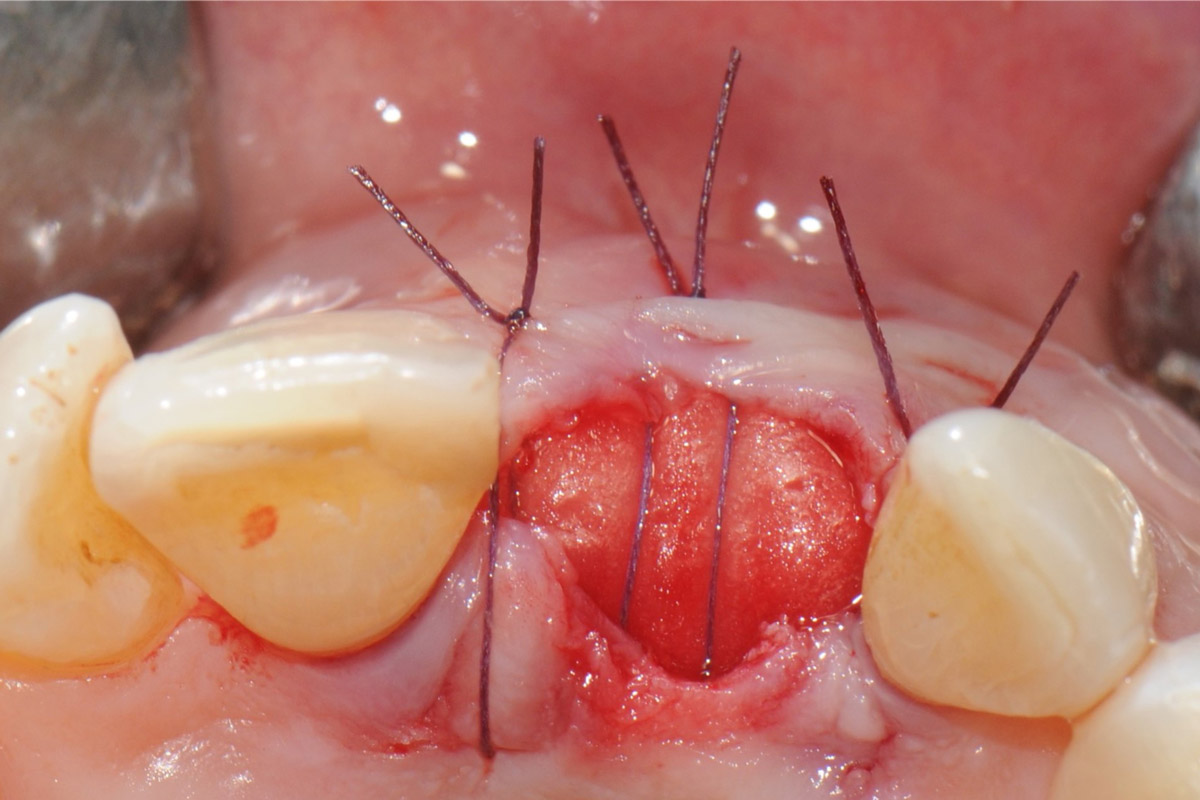

11/18 - Stabilization of the mucosal flap by nylon sutures 5/0Tooth extraction and socket sealing with mucoderm® - Dr. A. Rossi

12/18 - Occlusal view of the wound closureTooth extraction and socket sealing with mucoderm® - Dr. A. Rossi